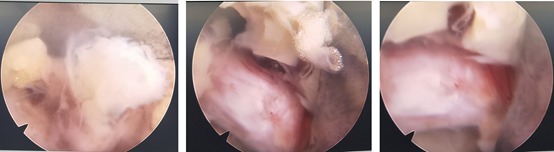

内镜下成功取出突出的椎间盘

手术当天,刘大姐就可以下地活动了,腰腿痛症状得到明显缓解。刘大姐也非常高兴,夸赞道“早知道这样,我就该早做手术。咱们科室不仅康复做得好,手术也做得好。我准备在这里继续做术后的康复,让我彻底告别腰椎间盘突出症的折磨。”